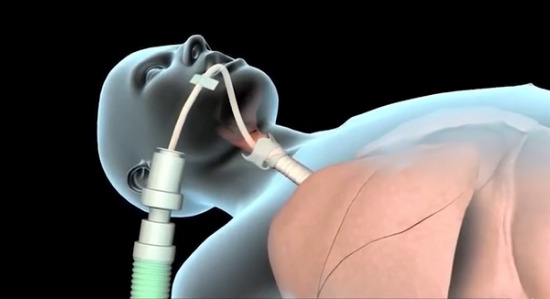

呼吸机

为了给免疫系统充足的时间与病毒斗争,避免因呼吸功能受损而引发其他症状。

根据阿里巴巴提供的《新冠肺炎防治手册》中提到的机械通气解决方案,一般会采用呼吸机来作为辅助器械。

这里的呼吸机数量就间接决定了患者的存活率,为了让更多人活下来,全球各地开始大量生产和购买呼吸机。比如,美国动用《国防生产法》要求通用汽车等公司生产呼吸机,类似的,德国大众,英国戴森,法国空客,日本丰田等企业纷纷响应政府号召生产呼吸机挽救患者生命。